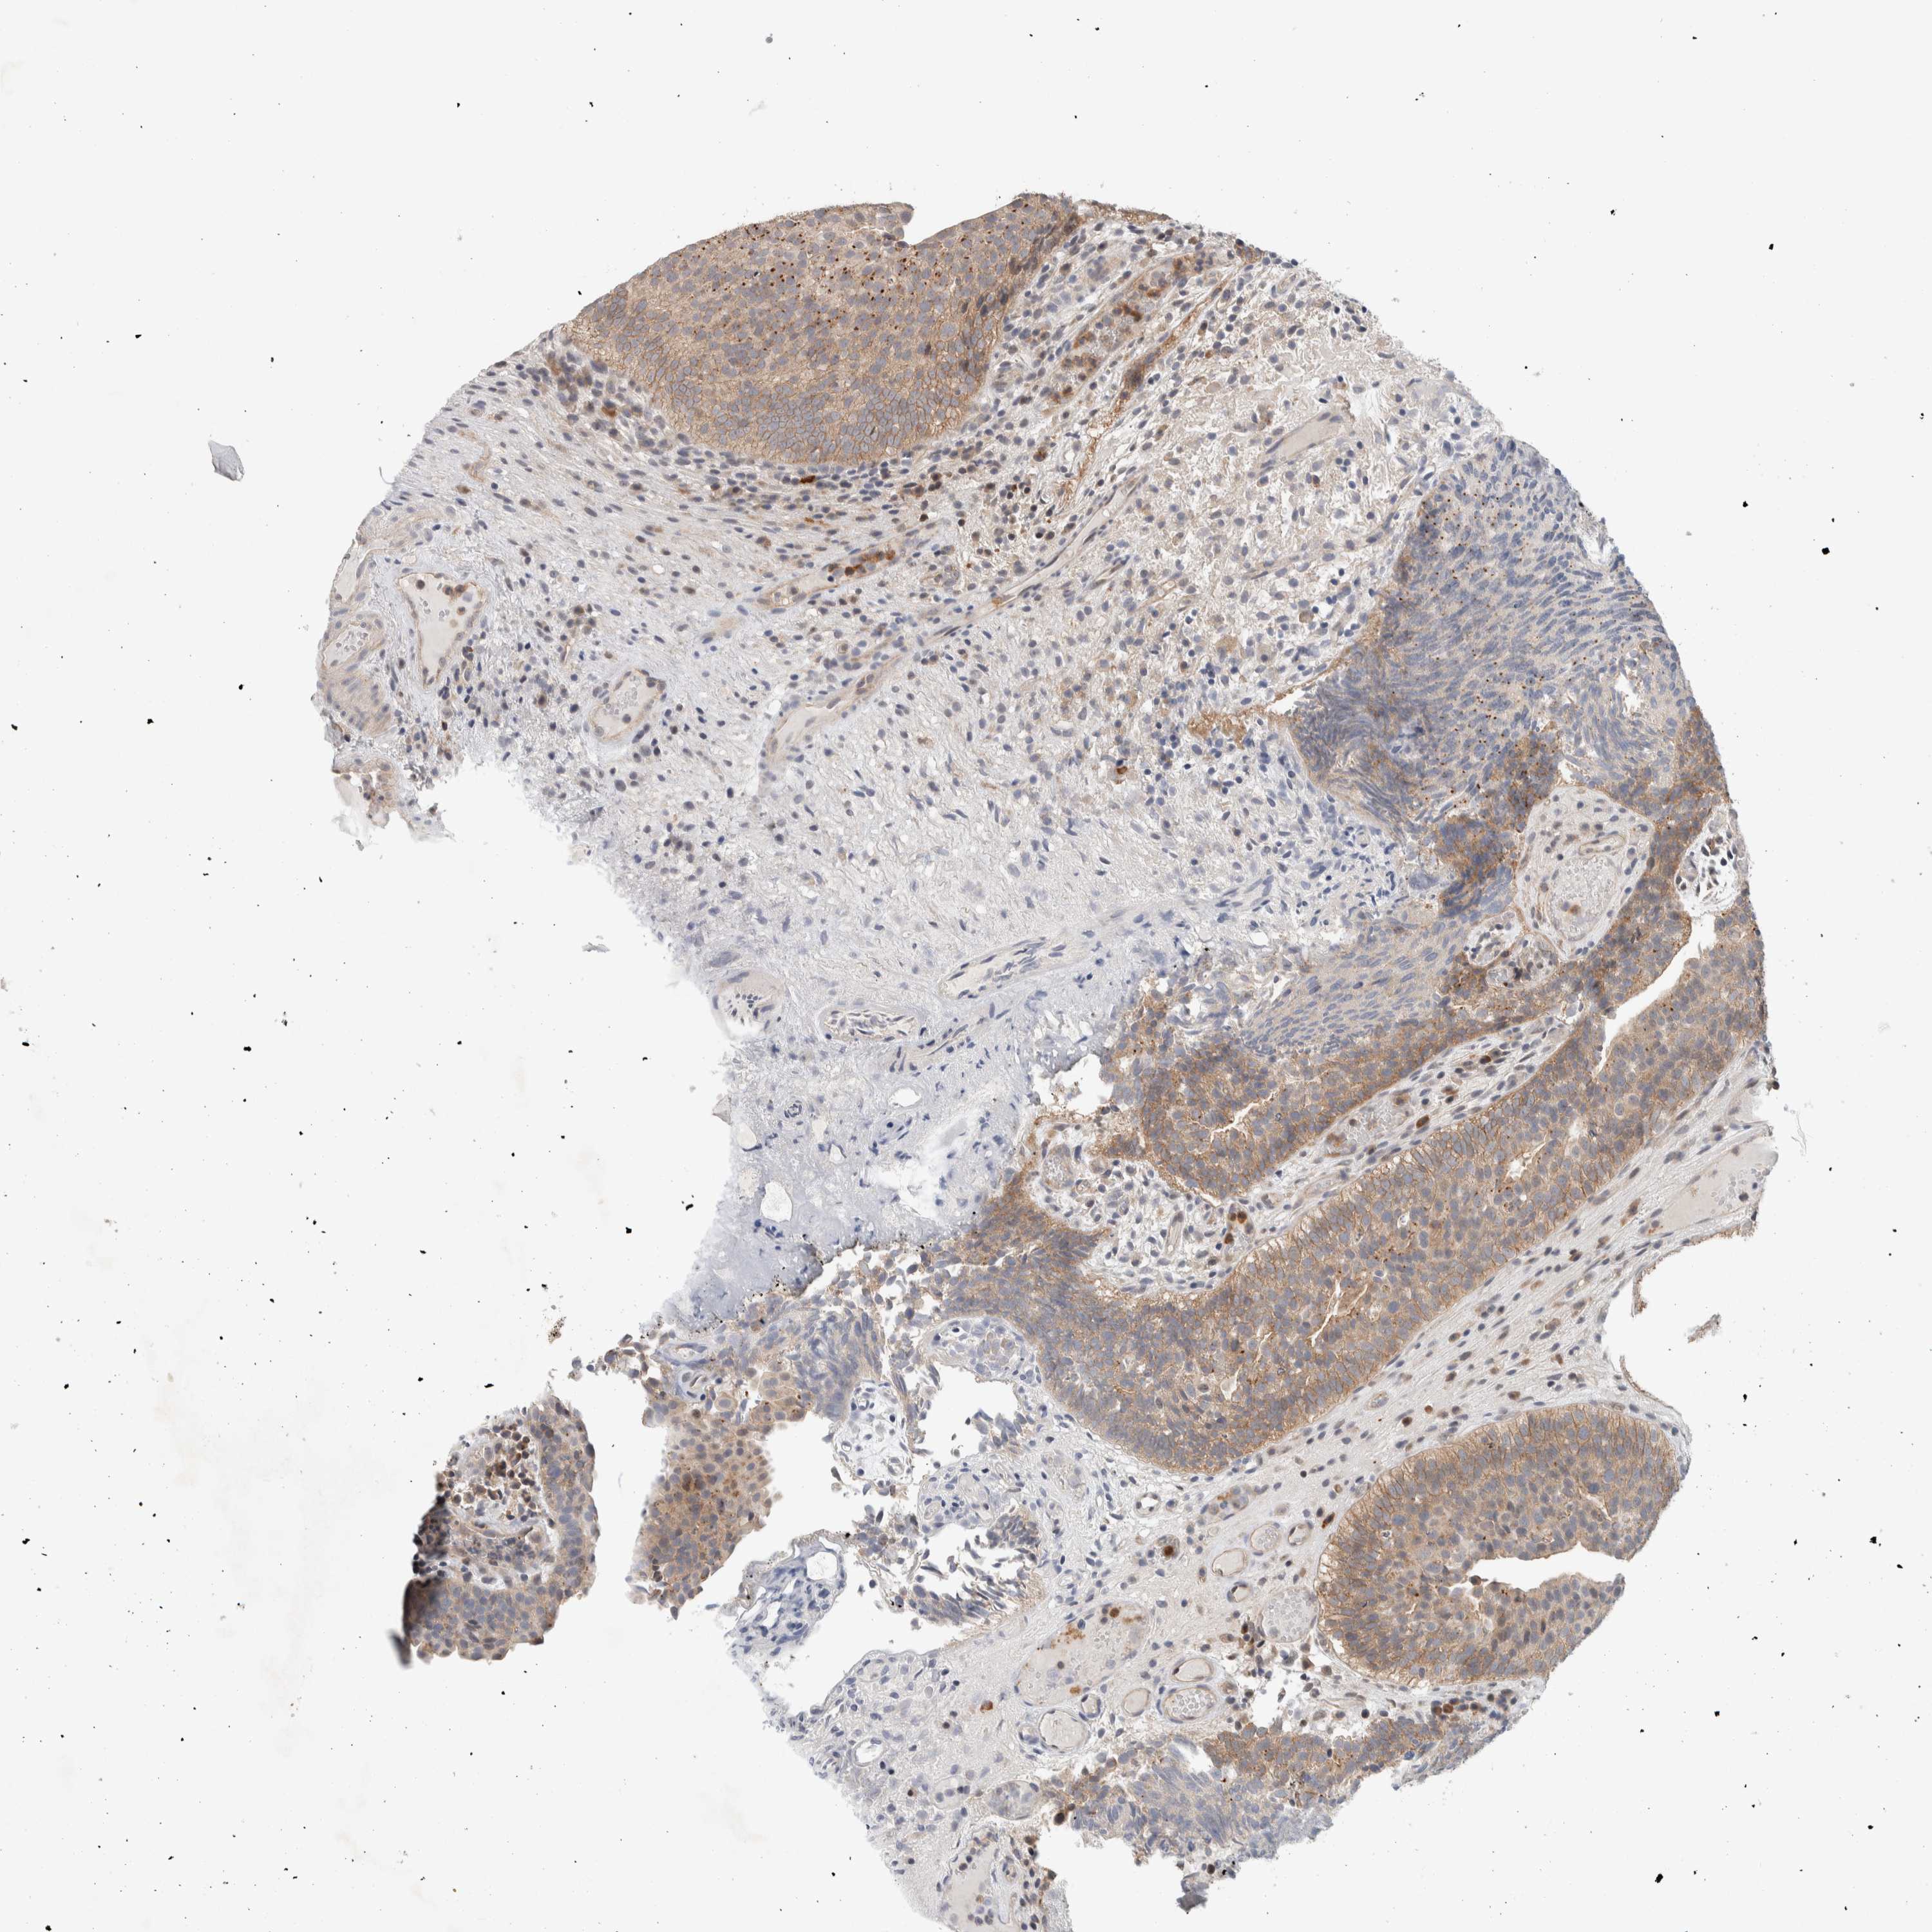

UROTHELIAL CANCER - Protein expressioni

A mouse-over function shows sample information and annotation data. Click on an image to view it in a full screen mode. Samples can be filtered based on level of antibody staining by selecting one or several of the following categories: high, medium, low and not detected. The assay and annotation is described here.

Antibody stainingi

Antibody staining in the annotated cell types in the current human tissue is reported as not detected, low, medium, or high, based on conventional immunohistochemistry profiling in selected tissues. This score is based on the combination of the staining intensity and fraction of stained cells.

Each image is clickable and will lead to virtual microscopy that enables deeper exploration of all samples and also displays staining intensity scores, fraction scores and subcellular localization as well as patient and tissue information for each sample.

Antibody HPA023938

Antibody HPA023945

Antibody HPA024011

Antibody CAB020841

Urothelial carcinoma, Low grade

Urothelial carcinoma, High grade